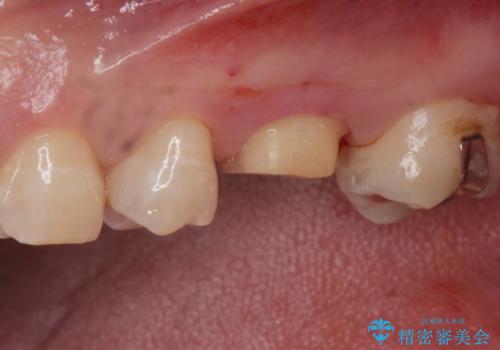

拡大鏡下でう蝕を全て取り除き、フルジルコニアクラウンで治療を行いました。

無事う蝕を全て取り除き、適合の良い白い被せ物が入りました。

銀の詰め物(保険)は歯質との隙間に細菌や汚れが入りやすく、う蝕の再発のリスクが高いです。